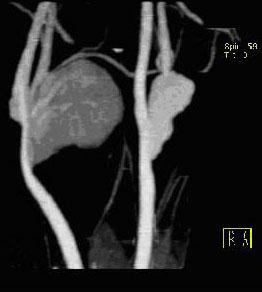

问题 男性,55岁,双侧颈部无痛性包块渐进性增大半年,行CT检查如图所示,请选择最佳答案 ( )

选项 A、双侧颈部肿大淋巴结 B、双侧血管瘤 C、双侧颈静脉瘤 D、双侧颈动脉夹层 E、双侧颈动脉瘤

答案 E